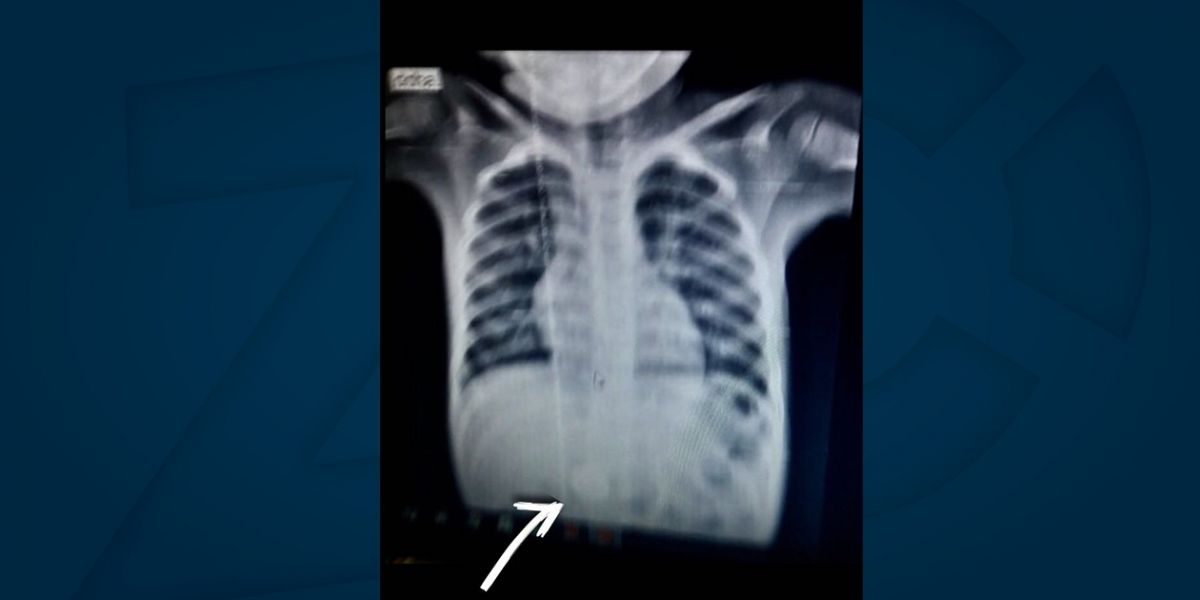

En condición estable se encuentra una menor de 4 años que accidentalmente se tragó una moneda, en hechos sucedidos en el municipio de Soledad (Atlántico).

La niña fue remitida hasta el Hospital Materno Infantil donde fue sometida a la atención requerida y luego dada de alta para la evacuación de la moneda por vía digestiva.

“La menor recibió la atención según protocolos para este tipo de eventualidades”, aseguró la Gerente del Hospital Materno Infantil, Claudia Arenas Torres.

Precisó que, afortunadamente, el incidente no comprometió la integridad de la menor, por cuanto la moneda se alojó en vías digestivas, facilitando de manera natural su expulsión.